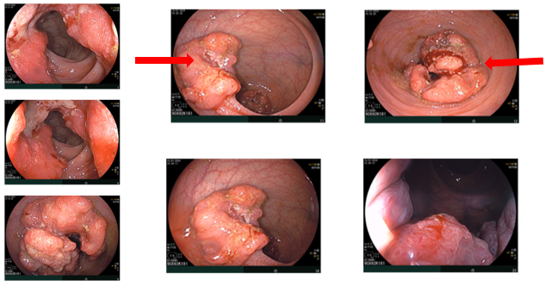

Cộng hưởng từ (MRI) vùng tiểu khung (07/2024):

Hình ảnh dày thành không đều quanh chu vi ở trực tràng cao–đoạn đầu đại tràng sigma; dày nhất khoảng 12 mm, trên đoạn dài khoảng 45mm; mất cấu trúc lớp thành ống tiêu hóa, kèm thâm nhiễm tổ chức mỡ xung quanh. Lân cận có vài hạch, hạch lớn khoảng 14×9 mm (tổng <7 hạch).

Hình 3: MRI vùng tiểu khung

MRI tiểu khung: Hình ảnh dày thành trực tràng giữa giảm còn trên đoạn dài 27 mm, chỗ dày nhất 8 mm; không thấy thâm nhiễm xung quanh, giảm so với 07/2024.